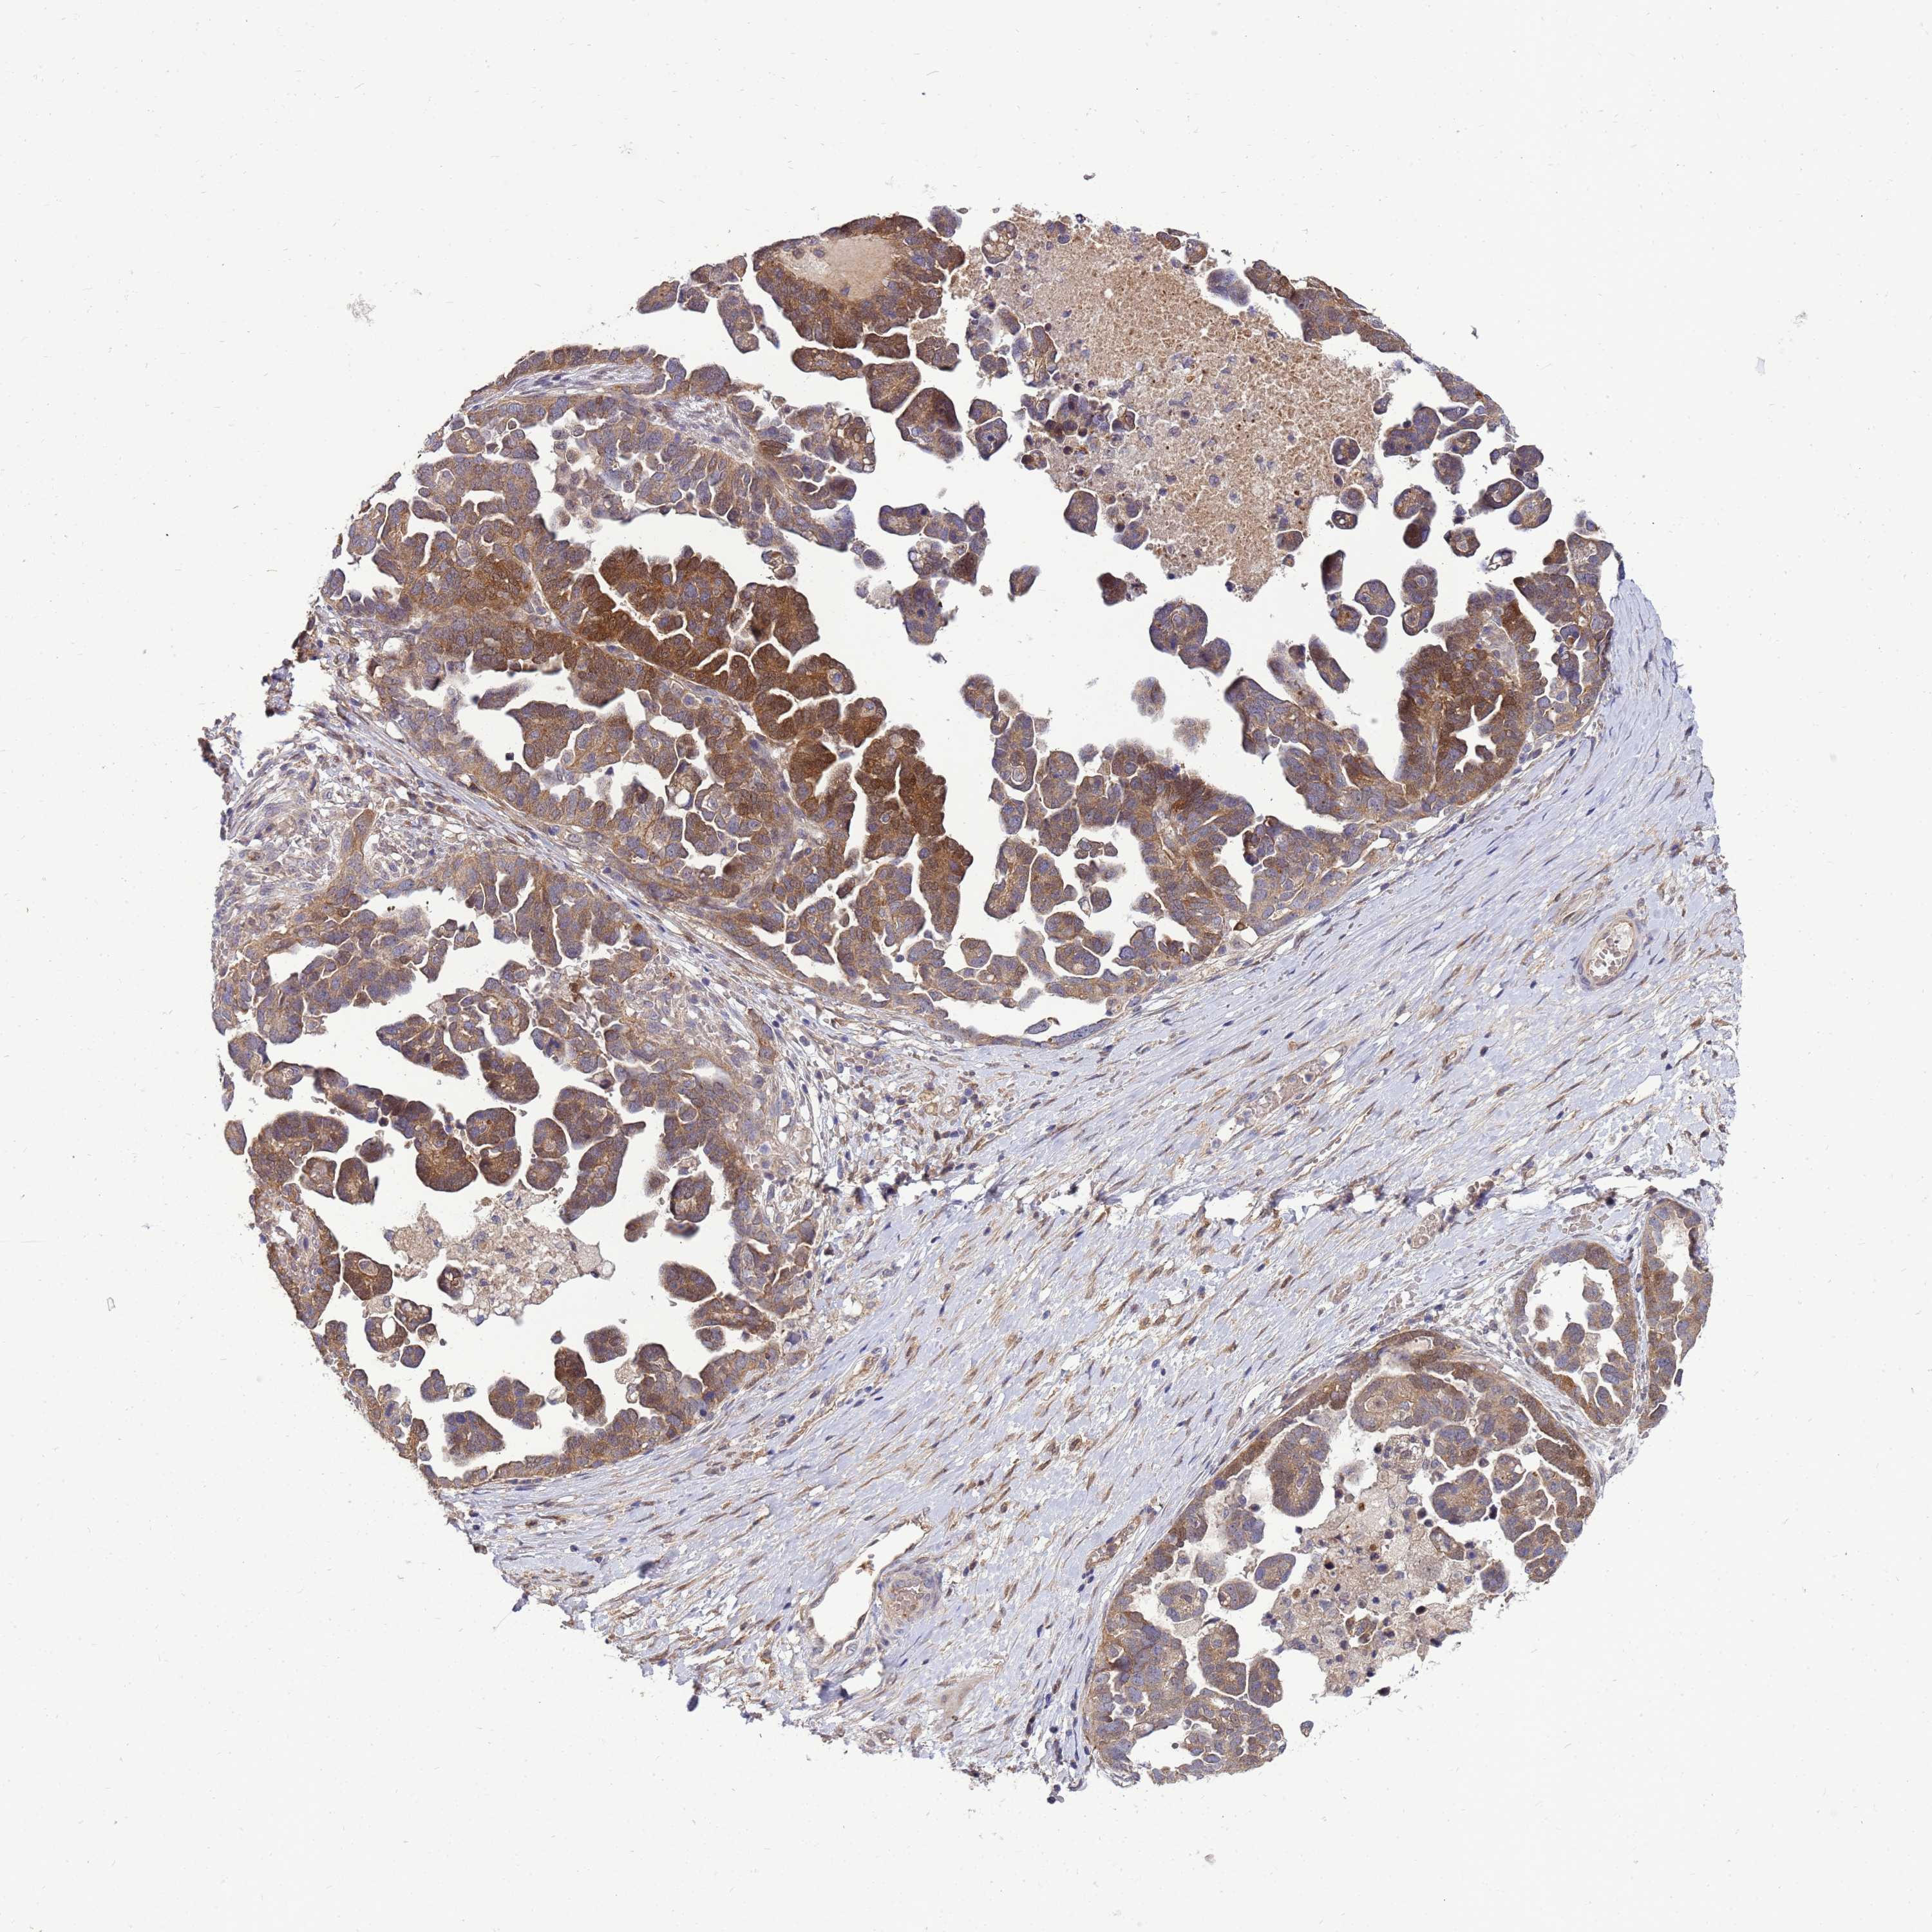

OVARIAN CANCER - Protein expressioni

A mouse-over function shows sample information and annotation data. Click on an image to view it in a full screen mode. Samples can be filtered based on level of antibody staining by selecting one or several of the following categories: high, medium, low and not detected. The assay and annotation is described here.

Note that samples used for immunohistochemistry by the Human Protein Atlas do not correspond to samples in the TCGA dataset.

Antibody stainingi

Antibody staining in the annotated cell types in the current human tissue is reported as not detected, low, medium, or high, based on conventional immunohistochemistry profiling in selected tissues. This score is based on the combination of the staining intensity and fraction of stained cells.

Each image is clickable and will lead to virtual microscopy that enables deeper exploration of all samples and also displays staining intensity scores, fraction scores and subcellular localization as well as patient and tissue information for each sample.

Antibody HPA045537

Staining

High

Medium

Low

Not detected

Intensity

Strong

Moderate

Weak

Negative

Quantity

>75%

75%-25%

<25%

None

Location

Nuclear

Cytoplasmic/membranous

Cytoplasmic/membranous,nuclear

Cystadenocarcinoma, serous, NOS

Carcinoma, NOS

Cystadenocarcinoma, mucinous, NOS

Carcinoma, endometroid